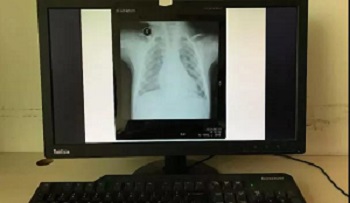

六、如果家里有电脑(台式机或笔记本电脑均可),也可以使用电脑显示器调白色后进行拍摄。使用电脑拍摄的时候,在电脑打开幻灯软件Powerpoint (PPT),新建一个空白文档,纯白色的,然后把该文档全屏播放模式下,即可实现全屏白色。